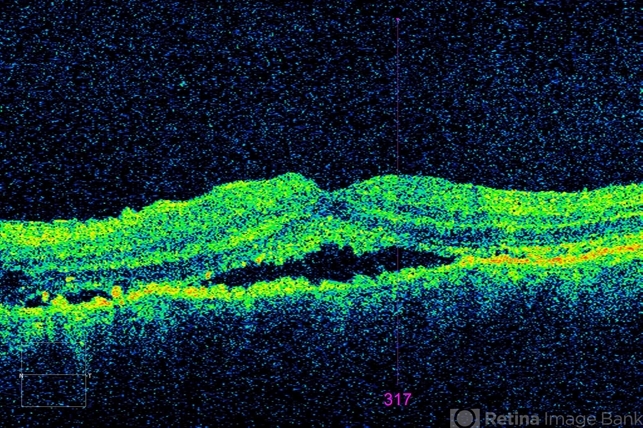

- Idiopathic Uveal Effusion Syndrome

- uveal effusion, idiopathic uveal effusion syndrome

- Dr. Angela Rico, Retina Specialists of Tampa

- Optical coherence tomography system

- 66 year old male presented with a 4 month vision of painless decreased vision in the left eye. Clinical findings consistent with idiopathic uveal effusion syndrome. Macular OCT shows presence of subretinal fluid.